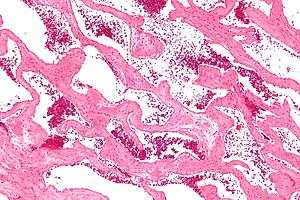

Usually the first step a doctor uses is an X-ray computed tomography (CT) scan to identify cavernous hemangioma. Magnetic resonance imaging (MRI) can be used to identify cavernous hemangioma. The phrase “bag of worms” is usually used to describe the appearance of hemangiomas in such images.[15] Angiography can be used by using a dye that is injected into the blood stream allowing for the contrast of hemangioma to show up. Additionally, doctors can use a biopsy by obtaining a sample of tissue of the tumor using a needle to examine it under a microscope. It is essential to diagnose cavernous hemangioma because treatments for this benign tumor are less aggressive than that of cancerous tumors, such as angiosarcoma. In some cases, it is possible for a surgery to be used as a method of diagnosis if imaging is not enough. The lesion is viewed under the microscope to diagnose cavernoma.[16]

Cavernous hemangioma, also called cavernous angioma, cavernoma, or cerebral cavernous malformation (CCM) (when referring to presence in the brain)[1] is a type of blood vessel malformation or hemangioma, where a collection of dilated blood vessels form a benign tumor. Because of this malformation, blood flow through the cavities, or caverns, is slow. Additionally, the cells that form the vessels do not form the necessary junctions with surrounding cells. Also, the structural support from the smooth muscle is hindered, causing leakage into the surrounding tissue. It is the leakage of blood, known as a hemorrhage from these vessels that causes a variety of symptoms known to be associated with this disease.

There are several known causes for cavernous hemangiomas, but some cases are still unknown. Radiation treatment used for other medical conditions has been suggested to cause cavernous malformation in some patients.[3] Hemangioma tumors are a result of rapid proliferation of endothelial cells and pericytic hyperplasia, or the enlargement of tissue as a result of abnormal cell division pericytes. The pathogenesis of hemangioma is still not understood. It has been suggested that growth factors and hormonal influences contribute to the abnormal cell proliferation. Cavernous liver hemangiomas are more commonly diagnosed in women who have been pregnant.[9] As a result of this, it is believed that estrogen levels may play a role in the incidence of liver cavernomas.